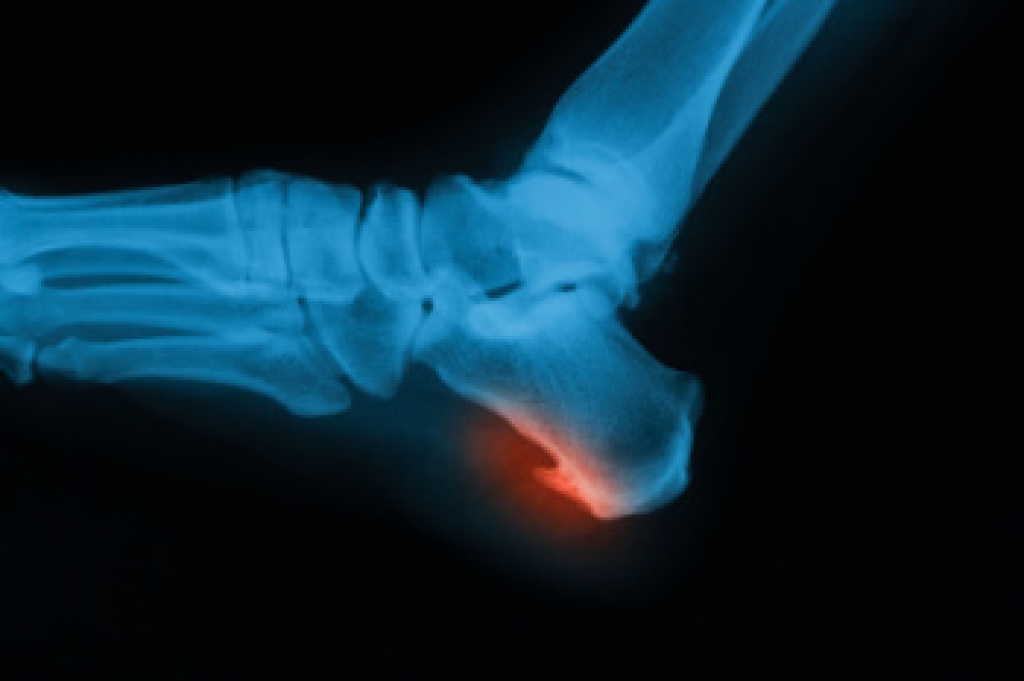

A heel spur is a bony growth that forms on the underside of the heel bone, often associated with chronic plantar fascia stress. Many patients experience sharp pain while standing or walking, especially first thing in the morning, although some may remain asymptomatic. Diagnosis typically involves a thorough physical examination and imaging tests such as X-rays to confirm the presence of the spur. Risk factors include prolonged standing, obesity, high-impact activities, flat feet, and tight calf muscles, all of which increase pressure on the heel. A podiatrist can provide effective treatment options, including custom orthotics, anti-inflammatory therapies, and minimally invasive procedures to relieve pain and improve mobility. If you have heel pain, it is suggested that you promptly consult a podiatrist who can accurately diagnose and treat heel spurs.

Heel spurs are formed by calcium deposits on the back of the foot where the heel is. This can also be caused by small fragments of bone breaking off one section of the foot, attaching onto the back of the foot. Heel spurs can also be bone growth on the back of the foot and may grow in the direction of the arch of the foot.